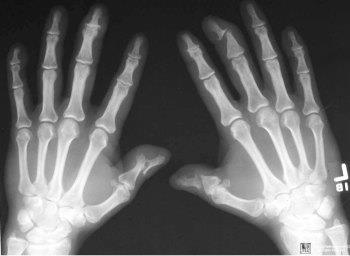

Обычно недуг встречается у людей в 20-50 лет. Чаще всего поражению подвергаются кисти рук и стопы. Нарушение функционирования опорно-двигательного аппарата способно привести к инвалидности пациента.

Чаще всего в дебюте заболевания отмечается изменение мелких суставов, расположенных на кистях и стопах, реже вовлекаются локтевые и коленные суставы. Довольно характерными симптомами псориаза суставов являются признаки дактилита, который является следствием воспаления сухожилий сгибателей и самих хрящевых поверхностей. Это состояние сопровождается:

Поражение суставов при псориазе может захватывать область голеностопа, коленей и пальцев. Чаще всего страдает не один, а несколько сочленений. Суставы болят, отекают (припухают), становятся розоватыми и горячими при ощупывании. Псориаз на суставах пальцев рук может протекать с выраженным отеком, когда пораженные пальцы становятся похожими на «колбаски».